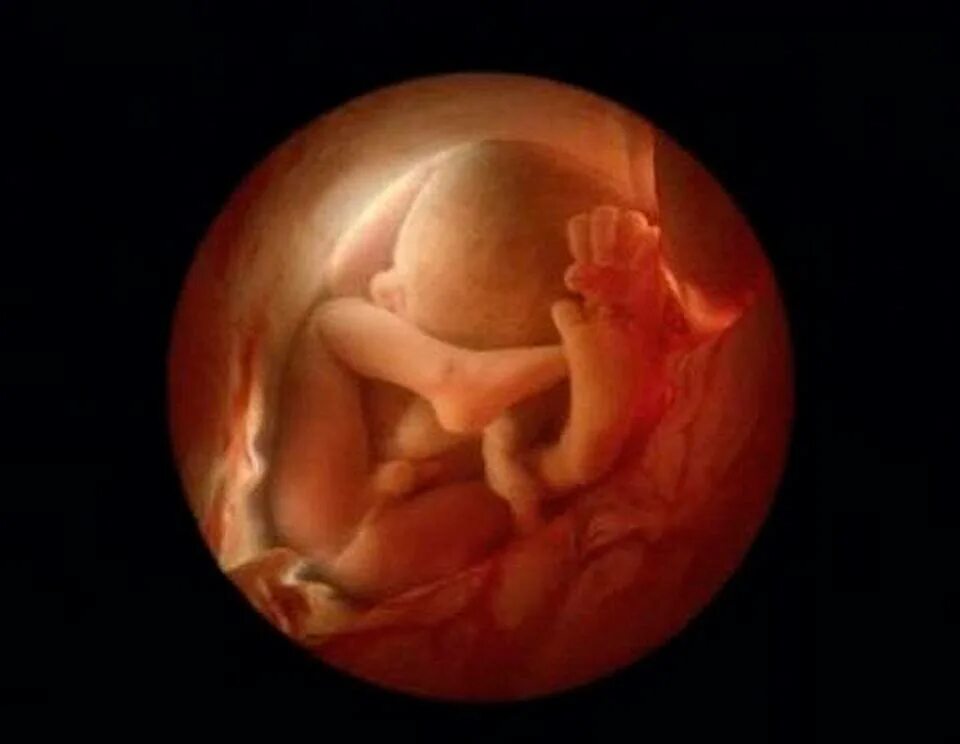

Через 20 недель